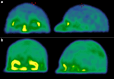

Method: The BREIN comparative study (NCT04328415) prospectively included patients with end-stage kidney disease (ESKD) and controls healthy volunteers matched in age, sex, and level of education to a patient. In all participants, BBB permeability was quantified by brain 99mTc-DTPA SPECT/CT as a percentage of injected activity (% IA). A battery of neurocognitive tests was performed, and serum uremic toxins accumulation and AhR activation were assessed.

Results: Fifteen patients with ESKD and 14 healthy volunteers were analyzed. Patients with ESKD had higher BBB permeability compared to controls: 0.29 ± 0.07 versus 0.14 ± 0.06 %IA, P = 0.002. Patients with ESKD displayed lower Montreal Cognitive Assessment test (MoCA) score: 22.0 ± 5.0 versus 27.3 ± 2.8, P = 0.008; impaired short-term memory (doors test): 12.5 ± 3.4 versus 16.5 ± 3.4, P = 0.005; higher Beck depression score 8.1 ± 9.1 versus 2.7 ± 3.4, P = 0.046; and slightly more daily cognitive complaints: 42.5 ± 29.3 versus 29.8 ± 14.0 P = 0.060. Patients with ESKD displayed higher IS levels (86.1 ± 48.4 vs. 3.2 ± 1.7 μmol/l, P = 0.001) and AhR activating potential (37.7 ± 17.8% vs. 24.7 ± 10.4%, P = 0.027). BBB permeability was inversely correlated with MoCA score (r = -0.60, 95% confidence interval [-0.772 to -0.339], P = 0.001) in the overall population.